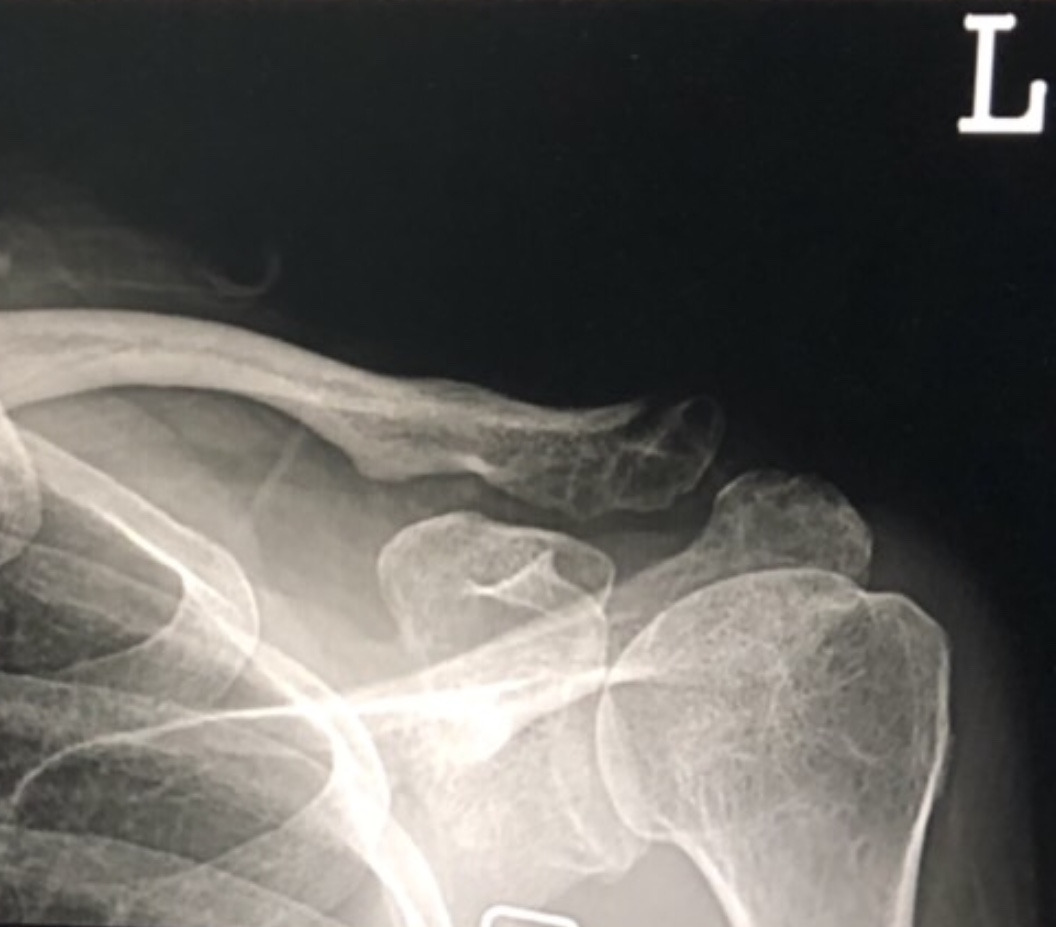

** 이 포스팅에는 쇄골 골절 관련 엑스레이 사진이 게재되어 보시기에 다소 불편하실 수 있습니다.

자전거 낙차로 인해 견봉단 쇄골 부위를 다친지 이제 11주차로 오늘 오전 진료를 받고 왔다. 개천절 휴일때문에 병원 대기실엔 많은 환자들이 차례를 기다리고 있었고, 나는 예약을 하고 갔는데도 30분 넘게 대기 중이었다. 호명을 받고 진료실에 들어서니 의사선생님께서 내 엑스레이 영상을 보고 "뼈가 다 붙었습니다. 수술 안하고 이렇게 붙었으니 얼마나 좋아."하며 나보다 더 기뻐해주셨다.

가만히 살펴보니 이제 엑스레이 영상으로도 뼈가 붙은 게 보인다. 아직 위쪽은 비어보인다고 질문하니 의사는 거긴 신경 안써도 된다고 한다. 달리기나 자전거 등 하고싶은 운동을 다 할 수 있으니 하라고 했다. 앞으로 도수치료 주 2회씩 받고 한달 후에 다시 진료를 받기로 했다.